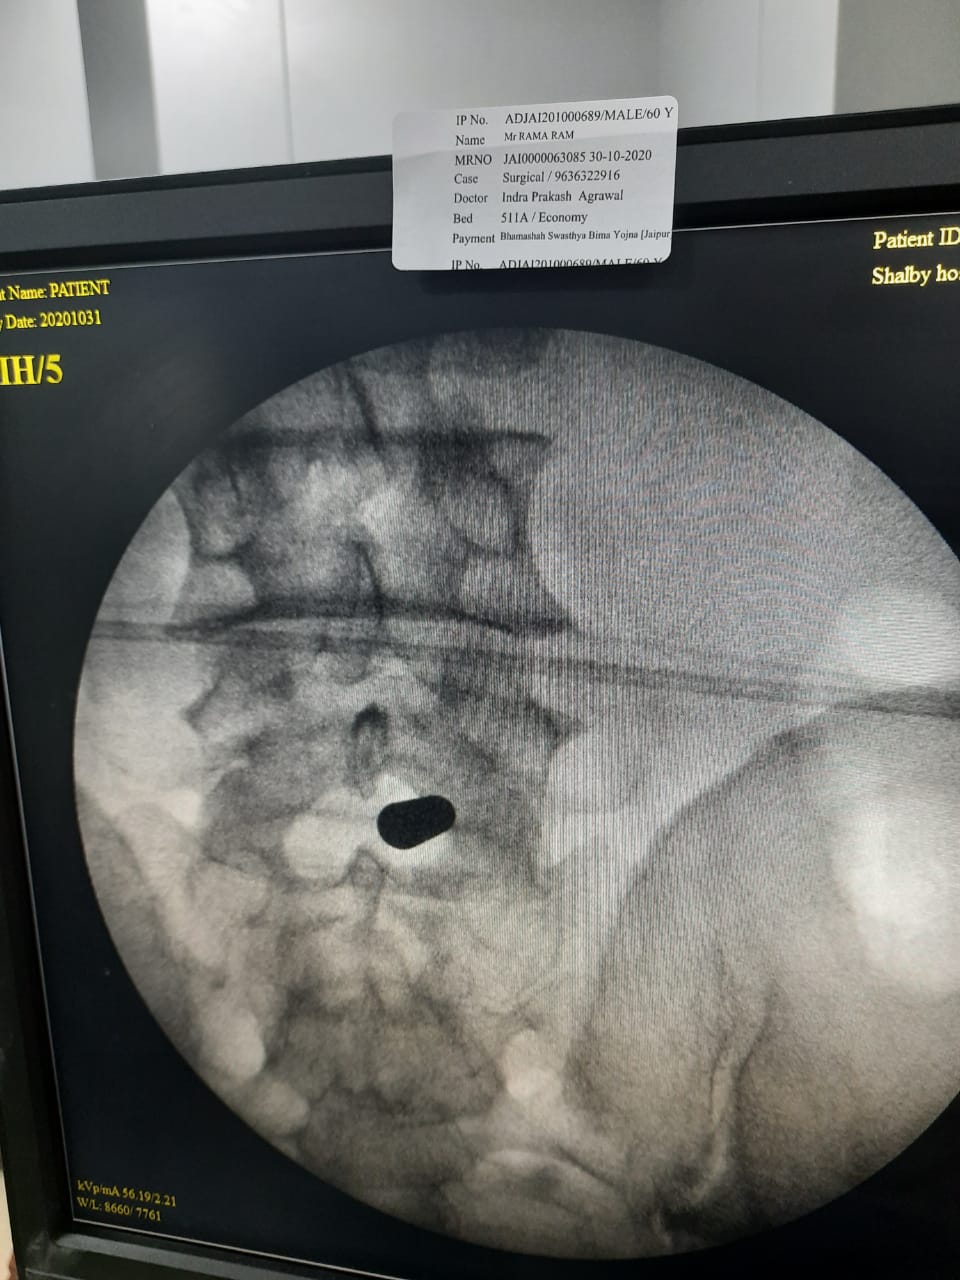

Here are some pics of our first case